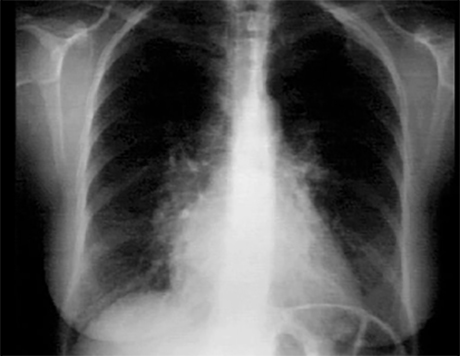

You are incorrect - the best interpretation of the chest X rays in our patient is right ventricular enlargement, prominent pulmonary arteries and decreased peripheral markings.

These chest X rays show right ventricular enlargement and left atrial enlargement. The PA view demonstrates left atrial enlargement reflected by the double contour within the heart border, an elevated main stem bronchus and an enlarged left atrial appendage causing straightening of the left heart border. Note also that the cardiothoracic ratio is greater than fifty percent, reflecting cardiomegaly.

In the lateral view, left atrial enlargement is further reflected by the prominent posterior left atrial shadow. right ventricular enlargement is best seen in this view and is manifested by obliteration of the retrosternal air space.